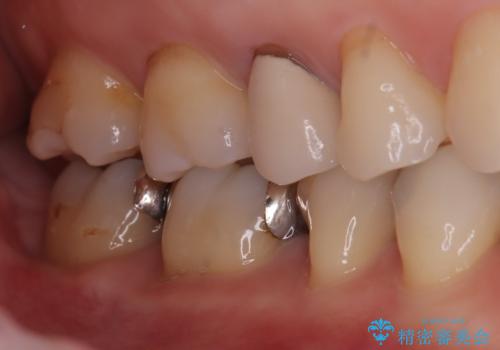

- 主訴:下の歯に入っている銀歯が笑うと目立つので白くしたい。

下顎臼歯部に入っている保険適用のメタルインレー(4箇所)を、審美性・適合性・清掃性の良いセラミックインレーにてやり替えました。